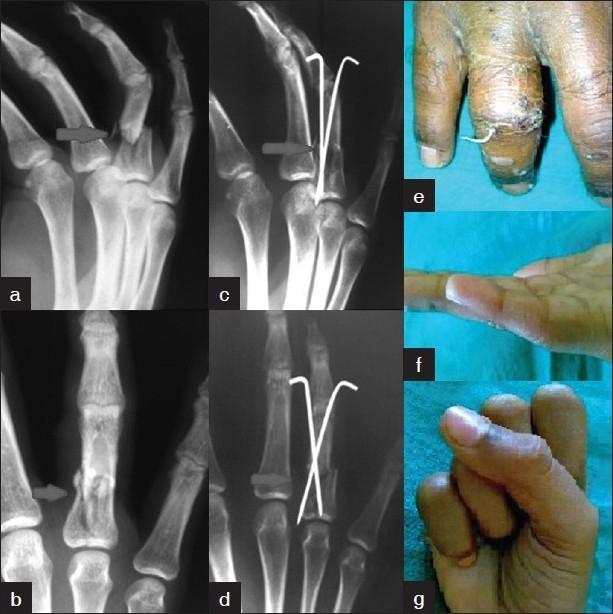

Eighty-four proximal phalangeal fractures in 68 patients were enrolled from 2007 to 2009. The treatment modalities were broadly categorised into two groups, Group A consisted of conservative treatment, and Group B consisted of surgical treatment. Group A included 47 digits treated with closed reduction (CR) with immobilization (n=43), extension block cast and dynamic traction (n=4), while 37 digits were treated in Group B, which included closed or open reduction (OR) and internal fixation (IF) with K-wires (n=31), OR and IF with stainless-steel wiring (n=2), and mini external-fixator (n=4). Belsky's criteria and Gingrass' criteria were used for assessment of finger injuries and to assess the efficacy of conservative and surgical modalities for closed proximal phalangeal fractures of the hand.

2007年至2009年纳入68例患者的84例近节指骨骨折。治疗方式大致分为两组,A组为保守治疗,B组为手术治疗。A组包括47指采用闭合复位(CR)加固定(n = 43)、伸展阻滞石膏固定和动态牵引(n = 4)治疗,而B组37指接受治疗,包括闭合或切开复位(OR)并用克氏针内固定(IF)(n = 31)、OR并用不锈钢丝IF(n = 2)以及微型外固定架(n = 4)。采用Belsky标准和Gingrass标准评估手指损伤情况以及评估保守和手术方式治疗手部闭合性近节指骨骨折的疗效。